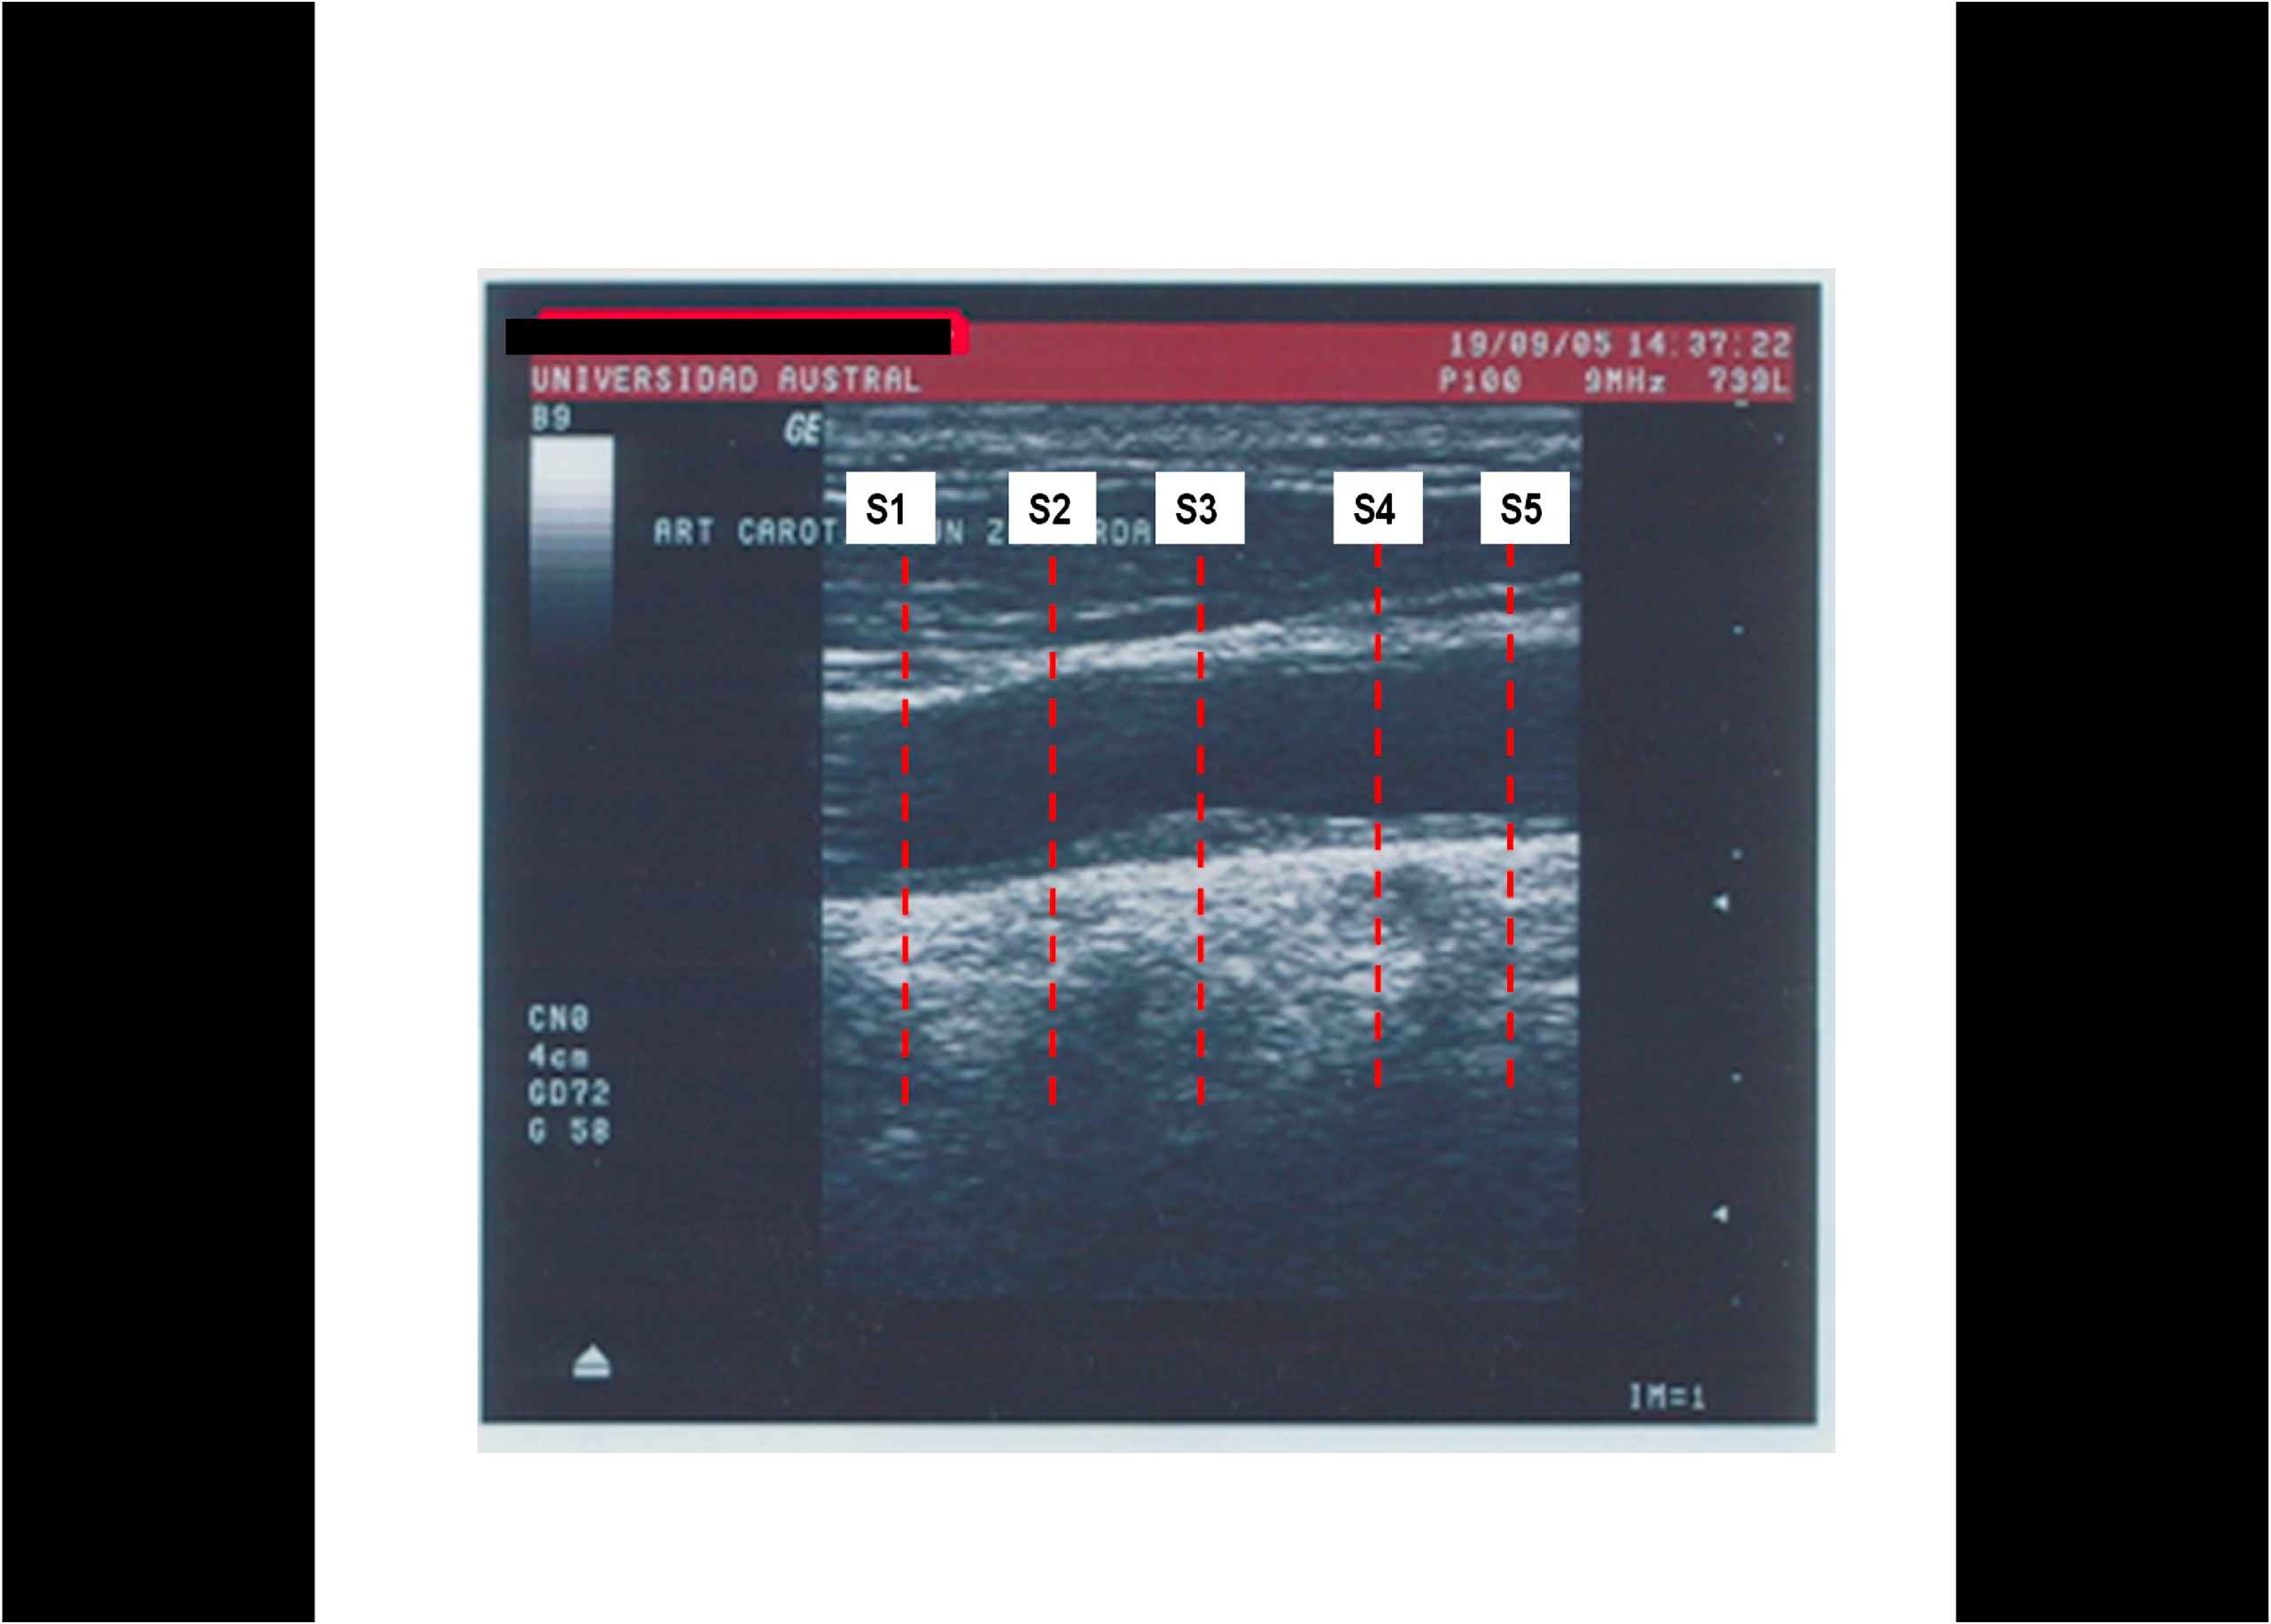

Methods: We selected 7 subjects (63±8 y.o.) with an echography of neck vessels (B mode and doppler, 10 mHz probe) similar baseline clinical and biochemical characteristics and AP in a common carotid artery (CCA). Five consecutive segments of the CCA, targeting the AP were evaluated (S1-S5 from proximal to distal, S3 the middle part of the plaque,S2 and S4 the proximal and distal shoulders). The instantaneous diameter and the signal of carotid pressure, calibrated with the brachial pressure (using a sphygmomanometer), were obtained and carotid Pressure / Diameter ratio, V, E and BC calculated.

Results: AP exhibited changes in V, E and BC. Biomechanical gradients were detected within the AP, being S3 the stiffer region (increased E, less V and BC, p< 0,05)